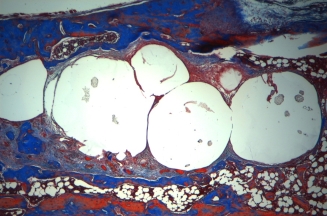

La thérapie cellulaire vise à soigner un tissu, un organe ou un organisme entier par l’apport de nouvelles cellules, obtenues et/ou modifiées à partir de cellules souches. Le but et de pouvoir remplacer ou suppléer des cellules défaillantes par de nouvelles cellules fonctionnelles. Les tissus peuvent alors se remodeler et fonctionner à nouveau.

Sa peau a pu être reconstruite principalement avec des greffes de peau autologue cultivée.

Une biopsie de peau de quelques centimètres carrés prélevée sur ce qui lui restait comme peau a permis de produire plus de 113 000 cm2 de greffe de kératinocytes et de fibroblastes. Sébastien Maillard a survécu grâce à la thérapie cellulaire.

objectif : régénérer la peau et accélérer la cicatrisation.